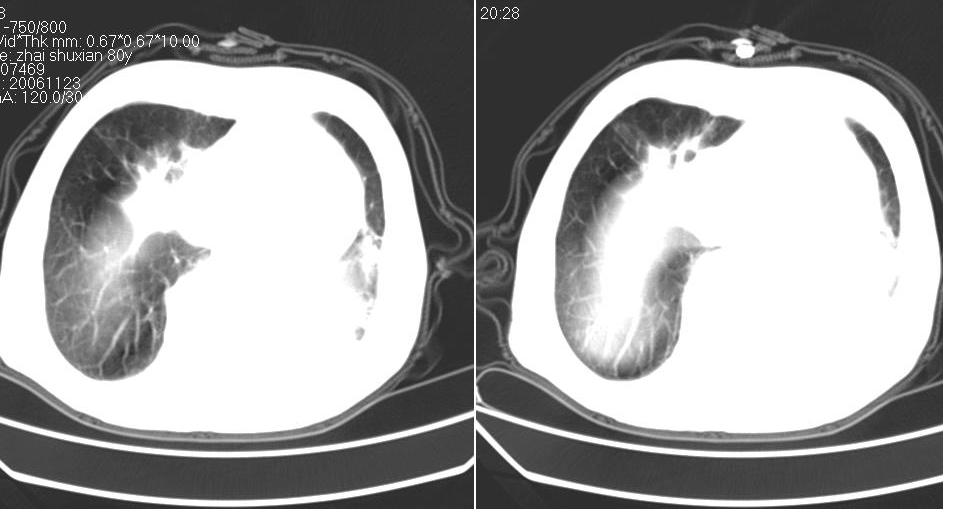

左下肺体积缩小,密度增高,见片增密影。边界模糊,见支气管充气像,肺门纵隔无异示,心脏气管左移,左侧胸腔少量积液。考虑肺部感染伴部分肺不张[有脑梗塞病史坠积性肺炎可能]

1、左肺下叶后基底段炎症并膨胀不全。

2、左侧胸腔积液。

左肺下叶体积缩小,成类楔形软组织影,其内可见部分含气支气管影,相应左侧肺门区未见明显肿块,考虑炎性病变,建议抗炎后短期复查

左下肺体积缩小,密度增高,并见大片状致密影,边界模糊,其内见支气管充气像,肺门纵隔无异常,心脏气管左移,左侧胸腔少量积液。考虑:左肺炎性病变伴不张。